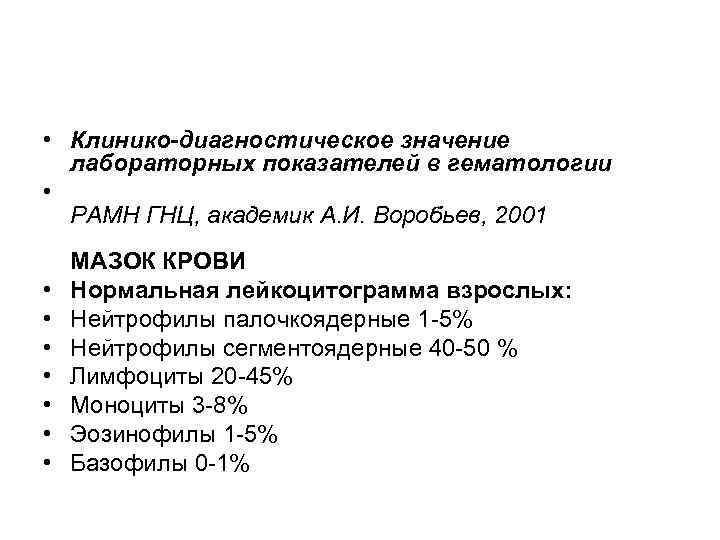

• Клинико-диагностическое значение лабораторных показателей в гематологии • РАМН ГНЦ, академик А. И. Воробьев, 2001 • • МАЗОК КРОВИ Нормальная лейкоцитограмма взрослых: Нейтрофилы палочкоядерные 1 -5% Нейтрофилы сегментоядерные 40 -50 % Лимфоциты 20 -45% Моноциты 3 -8% Эозинофилы 1 -5% Базофилы 0 -1%

• Клинико-диагностическое значение лабораторных показателей в гематологии • РАМН ГНЦ, академик А. И. Воробьев, 2001 • • МАЗОК КРОВИ Нормальная лейкоцитограмма взрослых: Нейтрофилы палочкоядерные 1 -5% Нейтрофилы сегментоядерные 40 -50 % Лимфоциты 20 -45% Моноциты 3 -8% Эозинофилы 1 -5% Базофилы 0 -1%

• В окрашенных мазках крови подсчитывают лейкоцитарную формулу + процентное соотношение разных видов лейкоцитов. Исследование лейкоцитограммы состоит в дифференциации в мазке 200 -500 расположенных подряд лейкоцитов.

• В окрашенных мазках крови подсчитывают лейкоцитарную формулу + процентное соотношение разных видов лейкоцитов. Исследование лейкоцитограммы состоит в дифференциации в мазке 200 -500 расположенных подряд лейкоцитов.